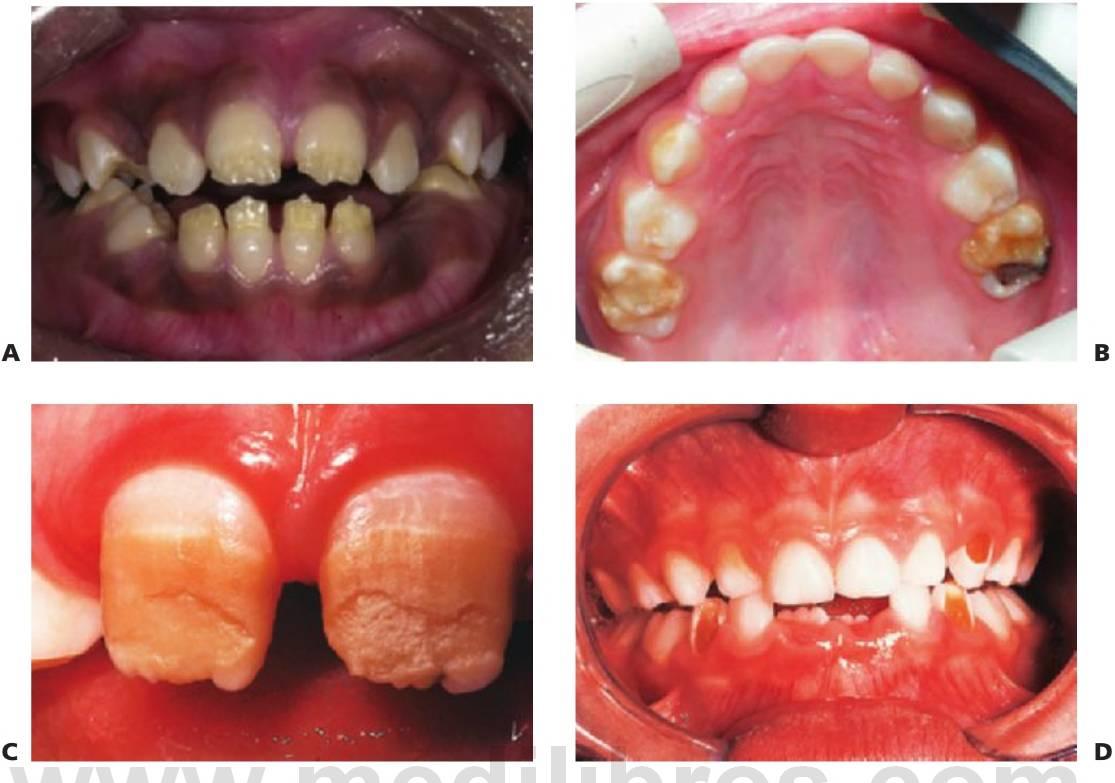

Amelogénesis imperfecta

El término amelogénesis imperfecta (fig. 9.25) suele aplicarse a defectos hereditarios del esmalte que afectan tanto a los dientes temporales como a los permanentes. La definición implica una historia familiar, pero en la práctica parece razonable ampliar esta definición para incluir los casos esporádicos y aquellos otros en los que los defectos del esmalte se asocian a manifestaciones extraorales, como ocurre en algunos síndromes (es decir, hipoplasia dérmica focal o síndrome trico-dento-óseo).

Fenotipos

Los fenotipos oscilan desde el esmalte (fino) marcadamente hipoplásico, uniformes (con espacios entre los dientes) o irregulares (dando lugar a pozos o surcos) hasta los diferentes grados de hipomineralización (esmalte muy mal formado) con alteraciones en su color y traslucidez. En muchos casos, la hipoplasia y la hipomineralización se presentan juntos. El color del esmalte refleja con claridad el grado de hipomineralización del mismo: cuanto más oscuro se presente el tono, más grave será la desmineralización.

En la amelogénesis imperfecta ligada al cromosoma X, las mujeres presentan franjas ver ticales de esmalte alterado como signo de lyonización (v. hipótesis de Lyon, descrita en este mismo capítulo). Pueden ser surcos verticales (debido a la hipoplasia) y/o bandas verticales de esmalte con el color o lucidez alterados (debido a la hipomineralización), o bien una combinación de ambos. En estas familias no existirá transmisión de varón a varón, pero las mujeres heterocigóticas pueden transmitir el rasgo a niños del mismo sexo.

En algunos pacientes afectados por amelogénesis imperfecta, los dientes no llegan a erupcionar, se cree que debido a una alteración del órgano del esmalte y sufren una reabsorción de sus coronas. En algunos casos (más del 50%) se observa una mordida abierta esquelética anterior.

Formas predominantes/exclusivas de la hipoplasia dental

- Esmalte fino.

- Ausencia de punto de contacto entre los dientes.

- El esmalte puede ser rugoso, liso o con pozos repartidos al azar.

- Las mujeres heterocigóticas con amelogénesis imperfecta ligada al cromosoma X manifiestan lyonización (v. antes) con franjas verticales de esmalte normal y anómalo.

- La erupción de los dientes se retrasa.

- Los dientes que no han erupcionado pueden reabsorberse.

- Mordida abierta anterior asociada en aproximadamente el 50% de los casos.

- En el plano radiográfico, puede resultar difícil distinguir el esmalte de la dentina si aquél es demasiado fino.

Formas predominantes/exclusivas de hipomineralización del esmalte

- El esmalte tiene un espesor normal, al menos inicialmente.

- El color es amarillo o pardo.

- El esmalte es más blando de lo normal, tiende a astillarse y se puede atravesar con un explorador. En los casos muy hipomineralizados, se puede arañar el esmalte con una cureta.

- Los dientes pueden erupcionar con un espesor normal, pero el esmalte se pierde pronto, dejando al descubierto una dentina rugosa y muy sensible.

- Se forman grandes masas de cálculo supragingival.

- En el plano radiográfico, resulta difícil distinguir el esmalte de la dentina debido al menor grado de mineralización del esmalte.

- Los dientes que no han erupcionado pueden reabsorberse, y se debe observar esta reabsorción mediante radiografías.

Tratamiento

- Diagnóstico apropiado, teniendo en cuenta el modo de herencia y el fenotipo.

- Compromiso de apoyo permanente a los niños y las familias. Se trata de cuadros dolorosos que desfiguran al niño y lo convierten en objeto de burla.

- Ofrecer consejo genético en caso necesario.

- Valoración ortodóncica temprana.

- Preservación de los molares con restauraciones de recubrimiento total para mantener la dimensión vertical. Las sobredentaduras pueden resultar una opción en niños con dientes hipoplásicos pequeños (fig. 9.27E, F).

- Coronas de acero inoxidable u onlays de oro en los molares (fig. 9.28). También puede resultar eficaz la elaboración de coronas, de composite en el laboratorio.

- Debe ponerse atención al ajuste de las coronas debido a que el esmalte defectuoso se astilla o descascarilla con facilidad en algunos casos.

- Carillas de composite en los dientes anteriores para conseguir una buena estética. Se puede adherir con éxito resina composite a un esmalte hipoplásico e hipomineralizado (figs. 9.27 y 9.28).

- Puede resultar difícil conseguir unos márgenes adecuados debido a la mala calidad del esmalte (fig. 9.28C).

- La ortodoncia, y puede que la cirugía ortognática, para corregir la mordida abierta anterior en las formas hipoplásicas.